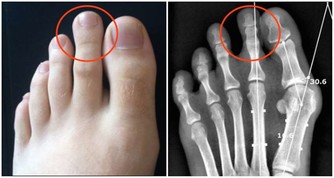

2、手足心多汗

若手足心多汗伴有手腳心熱、口咽乾燥等,多屬陰虛有熱。

若手足心多汗伴隨腹部脹痛,便秘,多屬腸道中有積糞的熱證。